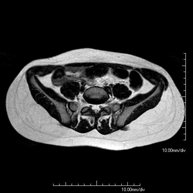

- RM Pelvis femenina

Prueba diagnóstica no invasiva que consiste en la obtención de imágenes de alta definición anatómica de la pelvis mediante el empleo de un campo electromagnético y ondas de radio (con un emisor y un receptor). No utiliza radiación ionizante. Se realiza para estudiar patologías del útero, del ovario, de las trompas y la vagina, ya sean de origen tumoral, inflamatorio o vasculares. Además permite valorar les estructuras adyacentes localizadas en la pelvis, identificando sus alteraciones. A veces requiere el uso de contraste intravenoso (Gadolinio) para caracterizar las lesiones.